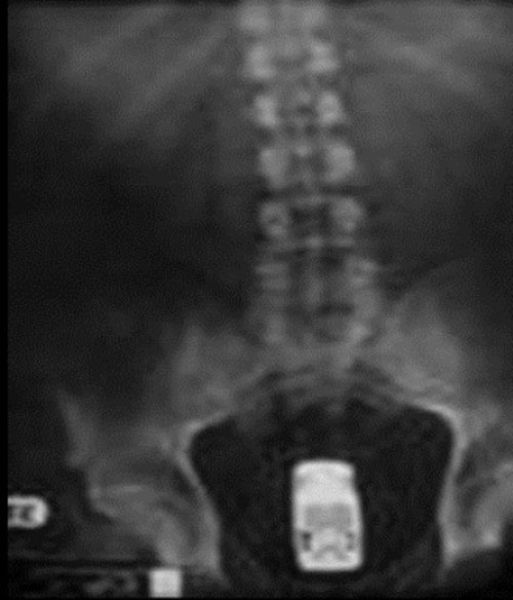

This X-ray reveals a cell phone lodged in a Salvadoran prisoner's lower intestine. The man is one of four prisoners who are members of the Mara Salvatrucha street gang. The men were caught with cell phones, spare chips and a charger that they had attempted to smuggle, according to authorities at San Salvador's Zacatecoluca prison.